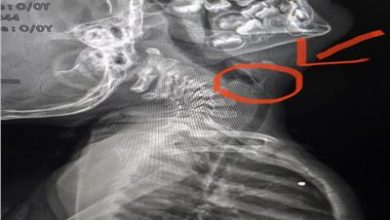

فريق طبي بمستشفى سوهاج الجامعى يستخرج شوكة سمكة من القصبة الهوائية لرضيعة عامين ونصف

كتب علاء حمدي قاعود نجح فريق طبي بمستشفى سوهاج الجامعي، من إجراء عملية جراحية لاستخراج شوكة سمكة من القصبة الهوائية…